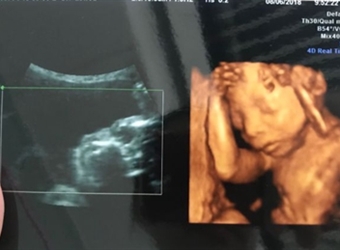

四维彩超是目前比较流行的孕检之一,四维能对胎儿头面部立体成像,可清晰显示胎儿的状态,网上很多四维是女孩但是却生了男孩的案例,那么四维女孩翻盘几率大吗…

四维彩超是实时的立体成像,在孕检的时候主要是帮助筛查胎儿的畸形,四维由于清晰度高也有用来判断胎儿男女,那么四维看是男孩有可能是女孩吗,四维男翻女的几…

四维彩超的报告中有很多的指标,网上也流传了很多通过报告单看男孩女孩的方法,那么四维胎儿双侧肾盂无分离是男是女,5个月四维如何看男女呢?更多关于生男生…

很多网上的宝妈都有看到这个情况,那就是做了四维彩超是男孩,但是却生了女孩,很多宝妈担心四维做的是男宝有可能翻盘吗,为什么四维男宝变女宝?更多关于生男…

网上有一种说法是,在做四维彩超的时候,如果是女宝宝是比较不容易配合的,如果是男宝宝更容易通过,那么是不是四维女宝更容易配合呢,四维女宝特征有哪些?更…

做四维彩超的时候,需要宝宝在肚子里动起来,有配合效果才是最好的,网上说做四维的时候不配合的都是女宝宝,那么这种说法是真的吗,四维是女宝还会翻盘吗?更…

很多宝妈都有在网上看到,做四维彩超的结果是女孩,但是最后生下的是男孩的案例,那么四维看是女孩最后会是男孩吗,女孩翻盘男孩的几率大不大?更多关于生男生…

网上流传着很多宝妈做四维彩超检查,医生说是男孩,但是结果生出来是女孩的案例,那么四维彩超男孩翻盘实例有哪些,为什么四维是男孩结果生女孩?更多关于生男…